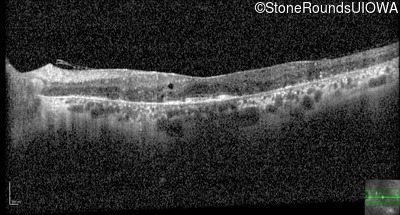

Age at visit: 53 years

OD OS